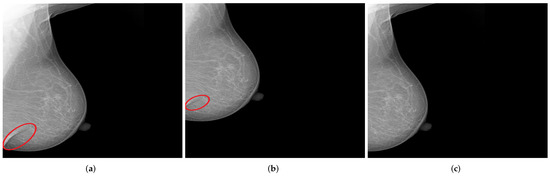

Image data augmentation is a technique used in deep learning algorithms to artificially increase the size and variability of a training dataset by creating modified versions of already existing images in the dataset. From the standard transformations, we applied random horizontal flips to introduce lateral (left or right) invariance. In addition, an automatic horizontal and vertical translation of the originally selected mammogram was used to generate new images with poor breast positioning quality even from an initially well-positioned mammogram (Figure 12).

Shift values for both translation types must be carefully selected to ensure that the features relevant for model prediction are preserved, as illustrated in Figure 13.

Figure 12. Generated mammograms with poor positioning quality by applying appropriate horizontal shift (b) and vertical shift (c) from an originally well-positioned mammogram (a). (a) Well-positioned mammogram (MLO view); (b) pectoralis muscle showing improper height and angle; (c) missing breast area in upper quadrant.

Figure 13. Examples of generated mammograms showing the significance of the selected shift value. (a) Original mammogram with a skin fold (cf. red circle); (b) created mammogram with a preserved skin fold (cf. red circle); (c) missing skin fold due to horizontal shift with an inappropriate value.